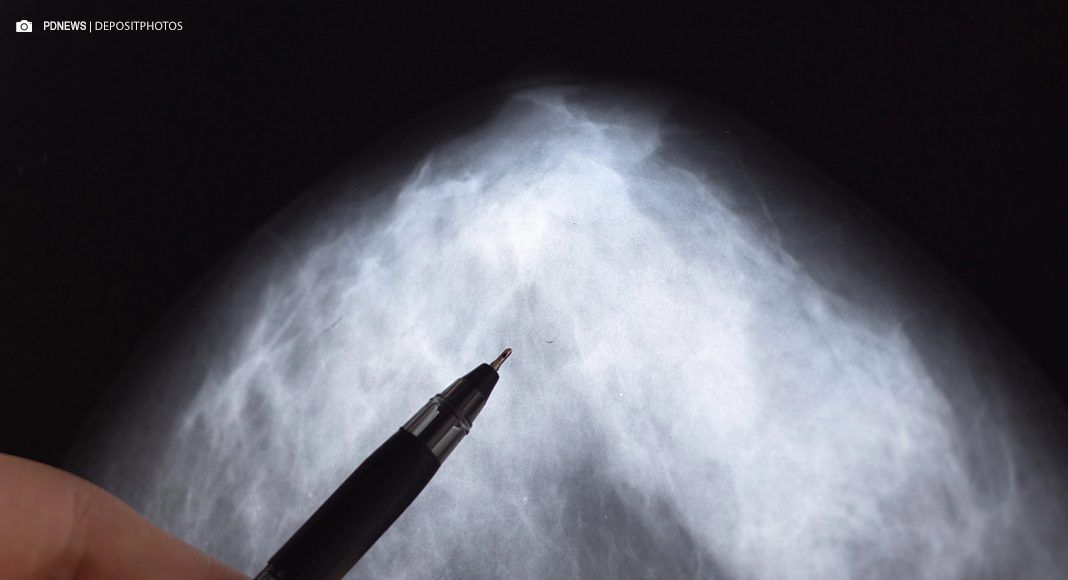

Na última segunda-feira, um encontro entre Agência Nacional de Saúde Suplementar (ANS), Federação Brasileira de Instituições Filantrópicas de Apoio à Saúde da Mama (FEMAMA), CBR (Colégio Brasileiro de Radiologia) e representantes de outras entidades médicas resultou na definição de novos critérios para certificação de qualidade, que deverão compor o rastreamento de usuárias de planos de saúde para o câncer de mama na saúde suplementar. Isso inclui a ampliação do rastreio individualizado para mulheres na faixa dos 40 a 74 anos. O intervalo dos exames de rastreio dependerá do médico solicitante e da vontade da paciente – um ano, dois anos ou até semestral em casos de forte histórico familiar de câncer de mama.

Entre outros critérios de qualidade acordados, consta que beneficiárias que possuem risco aumentado para o câncer de mama, de qualquer idade, poderão ser atendidas em rastreamento individualizado para a doença, conforme indicação médica e consentimento livre e esclarecido da paciente. Já para mulheres acima dos 74 anos, o rastreamento será individualizado, de acordo com a expectativa de vida da paciente. Consta também que as mulheres beneficiárias de planos de saúde serão alvo de uma busca ativa bienal promovida pelas operadoras, visando o rastreamento do câncer de mama para o segmento de 50 anos a 69 anos.